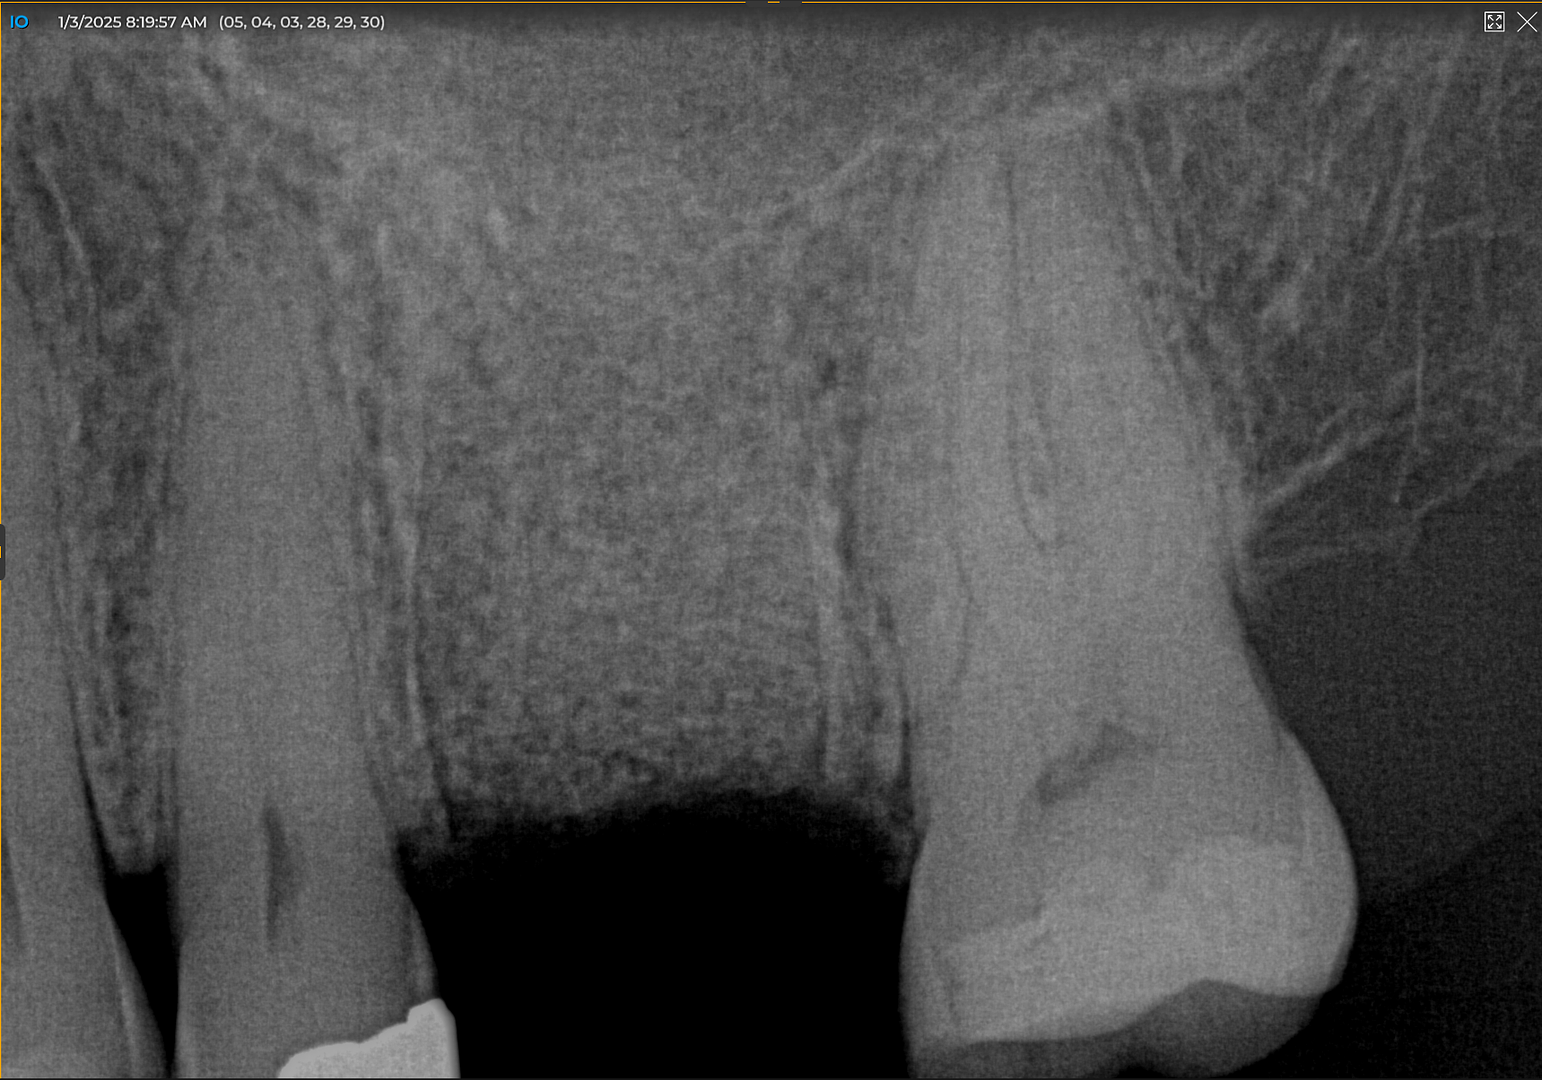

First, I layered a 20 × 30 collagen membrane and draped it from the buccal across to the palatal walls. Then I placed a 12 x 30 cytoplast PTFE membrane and secured both membranes with sutures. I wanted to leave the cytoplast for six weeks due to the size of the defect and graft, so I used both PTFE and glycolon sutures. The postoperative PA showed excellent bone fill that was dense.

At four months, patient returned and records were made for the implant process. Records showed good bone fill and good bone height, the implant was planned on exocad software and a guide was fabricated.